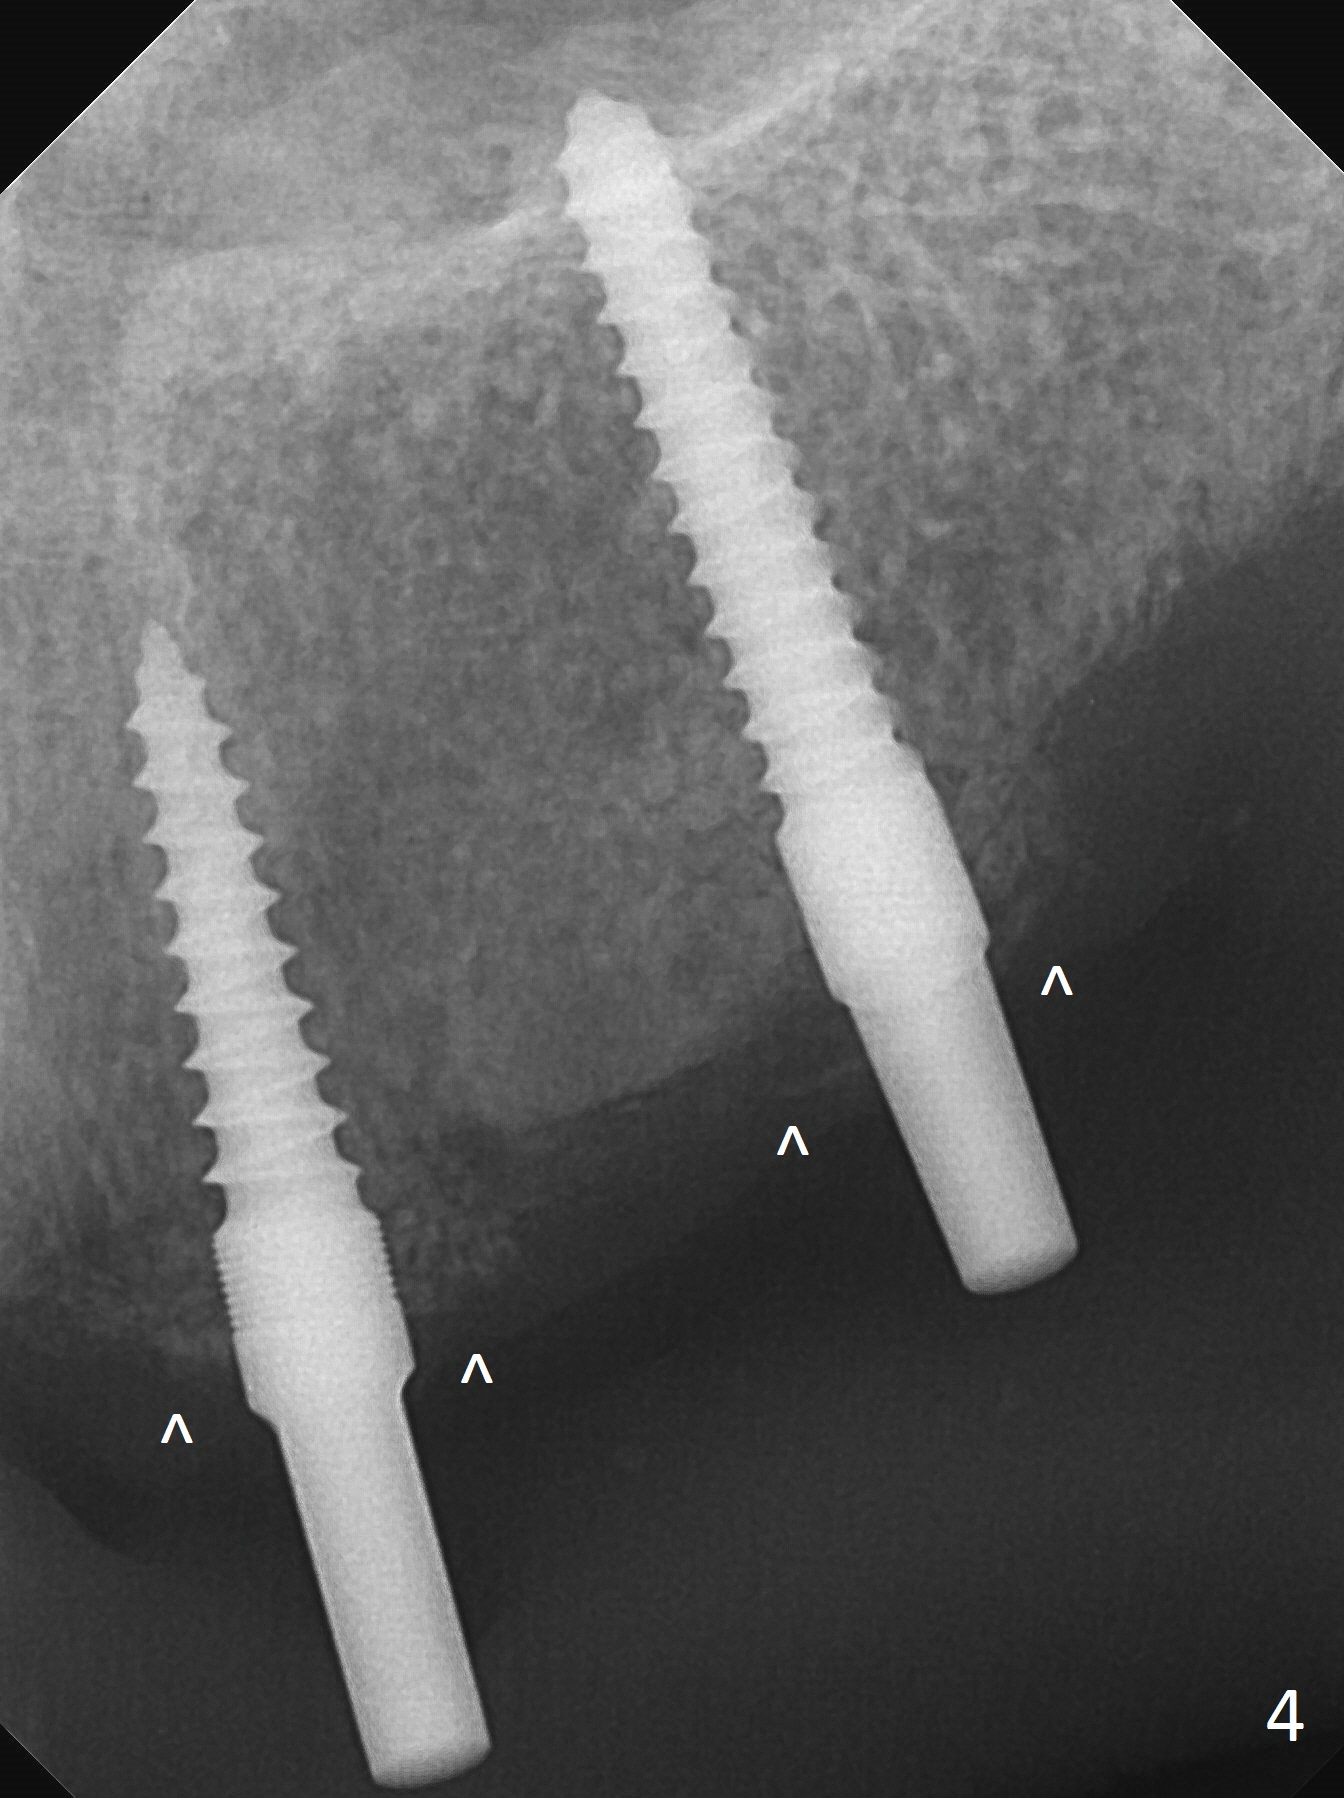

Incision reveals that the ridge at #9 and 11 is narrower than expected. A 3x14 mm 15º 1 piece implant is placed at the site of #9, while a 3x17 mm straight 1-piece one is placed at #11 (Fig.1,4). Insertion torques at #9 and 11 are 20 and 30 Ncm, respectively. The relatively low insertion torque is partially due to osteoporosis. The 65-year-old lady also has dry mouth. Osteotomy should be underprep. The position and trajectory of the implants are dictated by the partial denture (Fig.2). After minor abutment adjustment (Fig.3), an immediate provisional bridge is fabricated. There is no interference when the partial is removed and inserted. After bone graft (Fig.4 ^) and Osteogen Membrane, the ridge (Fig.3) is wider than before. The patient returns for reline 2 months postop (Fig.5-7). In spite of insufficient oral hygiene, the gingiva remains healthy around the implants. To form distinct papillae, acrylic should be added to (Fig.8 yellow line) and removed from (hushed area) the individual provisional crowns. One month after provisional modification (Fig.10, as compared to Fig.5), the pontic recipient site is concave (Fig.11) and becomes less concave after cord packing and abutment trimming. When the provisional bridge is reseated after impression (Fig.12), the pontic recipient site must be blanched again. Please trim the pontic recipient site of the model ~ .5 mm to enhance cosmetics. Water Pik has been used since surgery, but it may be related to loss of bone graft 3.5 months postop (Fig.9 *). One month post cementation, the patient has complained of pain when water pik is irrigating the gingiva palatal to the FPD, apparently in association with denture-related Candidiasis. Two weeks of use of Mycostatin Oral Suspension, peri-implantitis or peri-implant mucositis-like signs and symptoms disappear (Fig.13). CBCT taken 6 months postop confirms that the implants appear to be have been placed in the bone (14,15). The FPD appears to be loose 2.5 years post cementation.